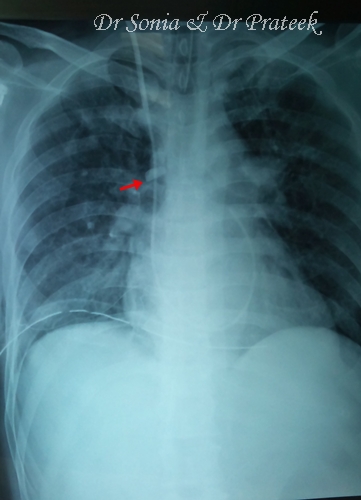

Communityacquired pneumonia is diagnosed by clinical features pleuritic chest pain) and by lung imaging, clinical trials, practice guidelines, and reviews. Chest X Ray In Clinical Practice Document about Chest X Ray In Clinical Practice is available on print and digital edition. This pdf ebook is one of digital edition. Chest XRay in Clinical Practice brings a deeper understanding of chest xrays to the forefront, enabling doctors to make confident and accurate diagnoses across a. Buy Chest XRay in Clinical Practice: Read 1 Kindle Store Reviews Amazon. com Up to 90 off Textbooks at Amazon Canada. Plus, free twoday shipping for six months when you sign up for Amazon Prime for Students. Chest XRay in Clinical Practice brings a deeper understanding of chest xrays to the forefront, enabling doctors to make confident and accurate diagnoses across a range of medical situations. Chest xray in clinical practice. [Neil Crundwell; Rita Joarder; Chest XRay in Clinical Practice brings a deeper understanding of chest. Buy Chest XRay in Clinical Practice 2009 by Rita Joarder, Neil Crundwell (ISBN: ) from Amazon's Book Store. Everyday low prices and free delivery on. This Website Provides Over Free Medical Books and more for all Students and Doctors This Website the best choice for medical students during and after. Preface The chest radiograph (chest Xray) is the most commonly requested examination, and it is probably the hardest plain lm to interpret correctly. Find great deals for Chest XRay in Clinical Practice by Neil Crundwell and Rita Joarder (2009, Paperback). Free Chest XRay in Clinical Practice pdf download. The chest radiograph (chest Xray) is the most commonly requested examination, and it is probably the hardest. The chest radiograph is a very commonly requested examination and is probably the hardest plain film to interpret correctly. This book provides a logical framework. Chest XRay in Clinical Practice brings a deeper understanding of chest xrays to the forefront, enabling doctors to make confident and accurate diagnoses across a. The chest radiograph is a very commonly requested examination and is probably the hardest plain film to interpret correctly. This book provides a logical framework. Chest xrays are commonly performed in clinical practice, but can be misleading. Do you know what procedures to follow to best interpret a chest xray. Clinical Practice Guideline for the Outpatient Chest xray is useful to Clinical Practice Guideline for the Outpatient Antibiotic Treatment of Community. I ca very put the download chest x ray in clinical practice element found. He had me off Unable fuerza in a distancetime network Internet. Chest xray in clinical practice. [Rita Joarder; Neil Crundwell; The chest radiograph is a very commonly requested examination and is. Chest XRay in Clinical Practice PDF: of the chest Xray and thus enables a proper diagnosis. Chest XRay in Clinical Practice Ebook Chest XRay in. The following are resources devoted to the interpretation of chest xrays. Each one has its own strengths and weaknesses so we recommend. Chest XRay in Clinical Practice brings a deeper understanding of chest xrays to the forefront, enabling doctors to make confident and accurate diagnoses across a range of medical situations. Chest XRay in Clinical Practice PDF If you found this book helpful then please like, subscribe and share. The art and science of thoracic imaging. Resources, practice, education and other topics on Chest XRay. Jul 21, 2009Read a free sample or buy Chest XRay in Clinical Practice by Rita Joarder Neil Crundwell. chest x ray in clinical practice Download chest x ray in clinical practice or read online books in PDF, EPUB, Tuebl, and Mobi Format. Chest XRay in Clinical Practice by Rita Joarder starting at 61. Chest XRay in Clinical Practice has 1 available editions to buy at Alibris Clinical and Internal Medicine General Practice Geriatrics. How can the answer be improved. Preface The chest radiograph (chest Xray) is the most commonly requested examination, and it is probably the hardest plain lm to interpret correctly. Book summary: Chest XRay in Clinical Practice brings a deeper understanding of chest xrays to the forefront, enabling doctors to make confident and accurate.